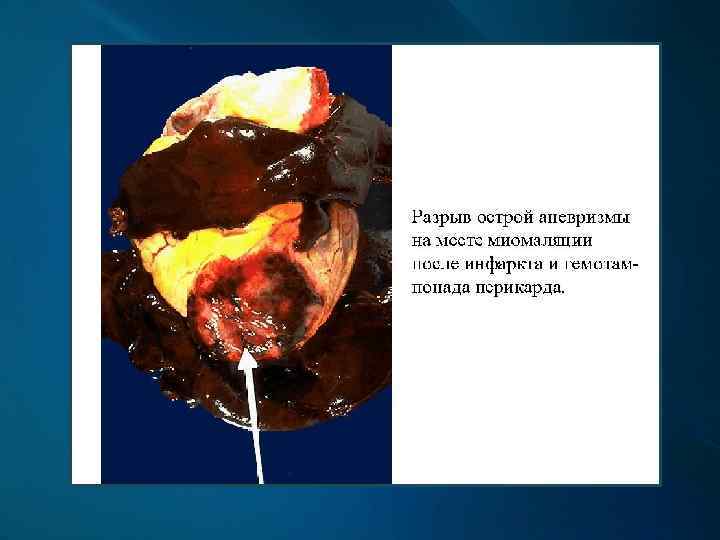

Макроскопически: первые часы - миокард дряблый, неравномерно кровенаполнен; через 18 -24 ч. – четко виден некроз; конец 1 -х сут. – некроз глинистокрасноватый, выбухает из-за отека, с геморрагическим венчиком; к 4 -6 сут. и далее – некроз западает, плотный, желто-серый, с красной каймой грануляционной ткани вокруг; через 3 -5 нед. – рубец красновато-серый, затем белесовато-серый.

Гемотампонада перикарда при разрыве стенки желудочка сердца

Макропрепарат сердца: постинфарктный кардиосклероз